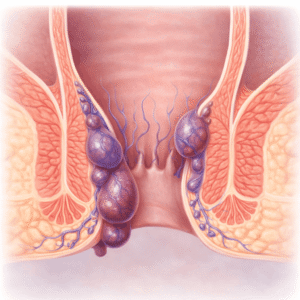

Haemorrhoid Relief: Home Remedies and Prevention Tips

Haemorrhoids affect millions worldwide, yet they remain a taboo topic. They can…

Read Article